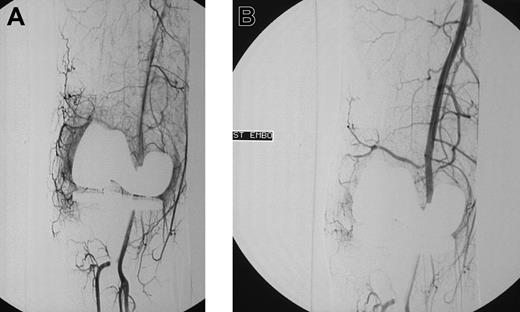

Blush in a patient with knee bleeding. Angiogram shows blush in a patient with recurrent massive knee bleeding following joint replacement before (A) and after (B) embolization.

Initial angiograms demonstrated a blush, indicative for hyperemic tissue as cause of bleeding in 15 patients (Figure 1A-B); in 2 patients a false aneurysm was observed (Figure 2A-B); in one patient a true aneurysm was observed; and in 3 patients an arteriovenous shunt in combination with an aneurysm was observed. In all these cases embolization of the feeding arteries was performed. However, in some cases, it was not possible to embolize all the bleeding arteries. In 2 patients, the cause of bleeding could not be localized (one patients with postoperative knee bleeding and one with spontaneous elbow bleeding) and embolization was not performed.